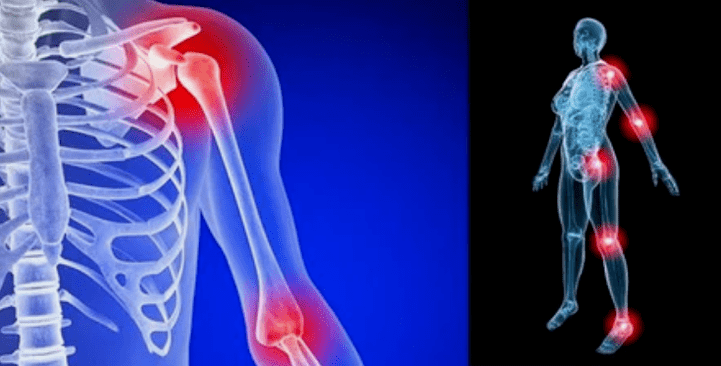

Haiguse ilmingud erinevad vähe, sõltuvalt lokaliseerimisest, sagedamini peegelduvad suure koormuse tõttu põlvedel, õla- ja puusaliigestel.